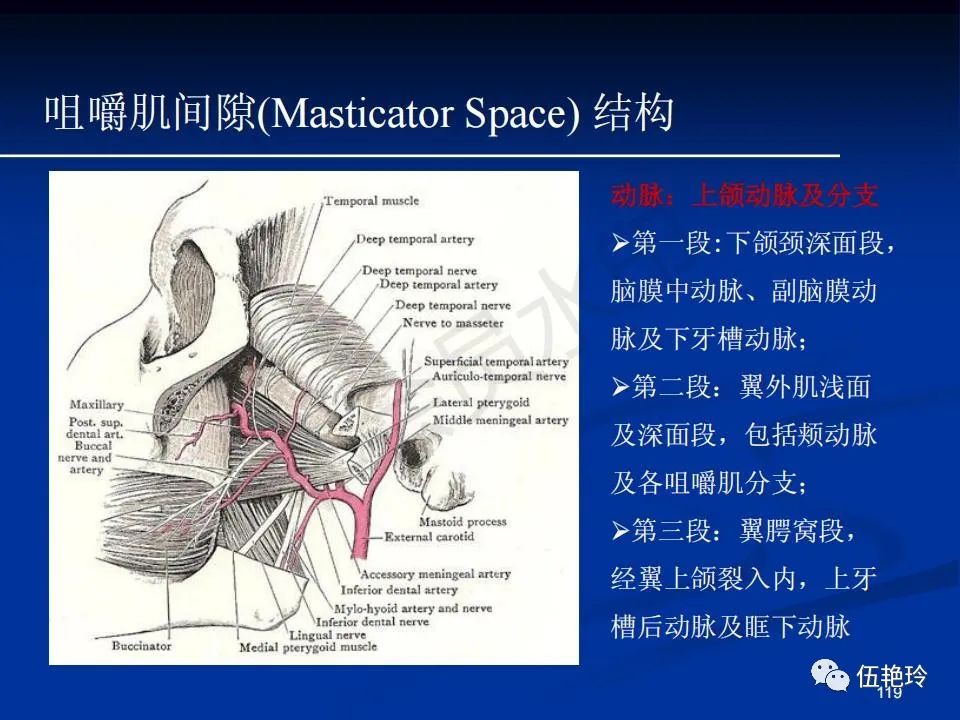

颞下窝与咀嚼肌间隙

2.31 向上颅内:①鼻咽顶壁→破裂孔(岩尖、斜坡)→蝶窦、海绵窦;②鼻咽顶壁→蝶骨基底部→蝶窦、海绵窦;③鼻咽侧壁→茎突前间隙→蝶骨大翼(卵圆孔)→海绵窦;④鼻咽侧壁→茎突前间隙→翼腭窝→ 颞下窝;⑤鼻咽前壁→鼻腔→翼突、翼腭窝→眶下裂→眶尖→海绵窦;⑥鼻咽前壁→鼻腔→上颌窦、筛窦;